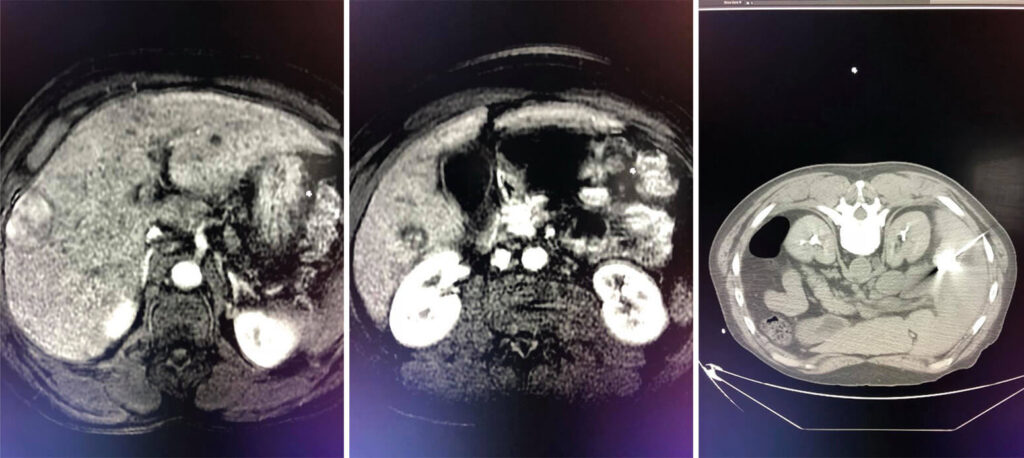

Case of the week: 56 year old with multi focal Hepatocellular Carcinoma with 3 liver masses. Staged treatment with CT guided microwave ablation followed by intra-arterial chemoembolization (chemotherapy coated beads injected directly into the blood supply of the liver). Great stuff Dr Meka!!